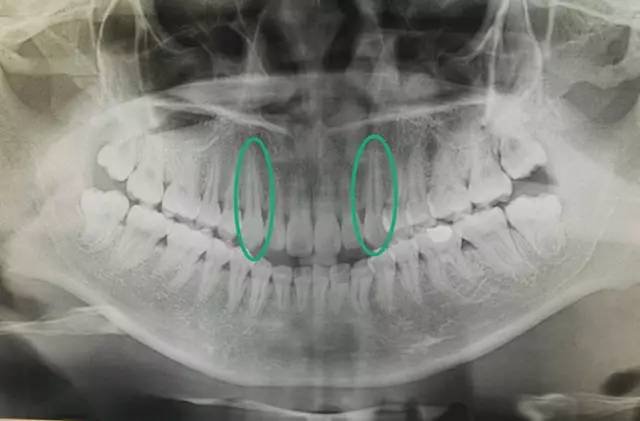

从图中能够看出,尖牙长出的时间是在侧切牙和第一前磨牙之后的

如图,尖牙是所有牙齿当中牙根最长的